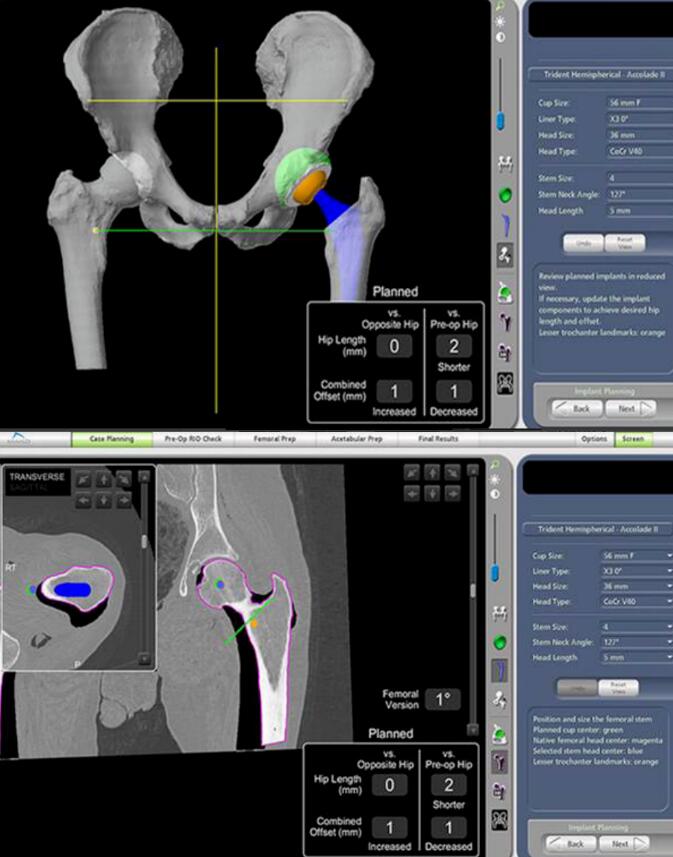

Mako智能机器人是一款基于智能手术规划技术和智能辅助截骨技术的关节手术机器人,系统囊括了临床诊断、术式设计、手术虚拟仿真、疗效评价、手术导航和远程医疗等。

机械臂、导航模块和摄像立架是Mako机器人的核心组成部分,它们犹如人的“手臂”、“大脑”和“眼睛”,将传统的手动手术过程转化为数字化规划,通过“术前完整的手术规划”、“术中1度和1毫米的精准截骨与假体植入”,实现人工关节的高精度植入,使其完美适配人体关节的生理结构与活动需求,达成“精准微创、加速康复”的治疗目标。

利用患者术前CT数据构建3D骨骼模型,通过导航模块在专属3D模型图像上规划植入物尺寸与摆放位置,对安装效果和截骨量、截骨角度等进行提前“预演”,实现精准术前方案定制。

2、术中:实时动态平衡与智能防错

手术中系统实时捕捉软组织张力,关节面的接触点,髋关节的前倾角,下肢长度,旋转中心,偏心距等临床信息,医生据此调整手术计划,实现关节平衡并达到1度1毫米个性化放置。当操作偏离预设路径0.1毫米,机械臂触发阻力反馈、警报并终止操作。